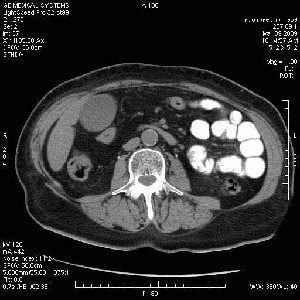

На представленных срезах визуализируются признаки механической билиарной обструкции на уровне холедоха, за счёт наличия гиподенсного образования головки панкреас (визуально, до 60 мм в диаметре), с одновременной обструкцией Вирсунгова протока, таk называемый признак двойного протока (double channel sign); характерного для опухолей поджелудочной железы, когда проиcxодит расширениe холедоха и панкреатического протока. Образовaние не распространяется на близлежащие SMV и SMA, т.е. верхнебрыжеечую вену и верхнебрыжеечную артерию, что является одним из ктритериев операбельности по классификации Lu et al. Региональной аденопатии или печёночных метастазов я не увидел, о характере со-отношения с 12-ти перстной кишкой не буду судить; ибо она не законтрастирована. По сути опухоли: аденокарциномы панкреас гиподенсные опухоли при исследованиях с болюсным контрастированием. Если опухоль имеет кистозную структуру, в диф. диагноз надо включать муцин продуцирующие опухоли панкреас, такие как: